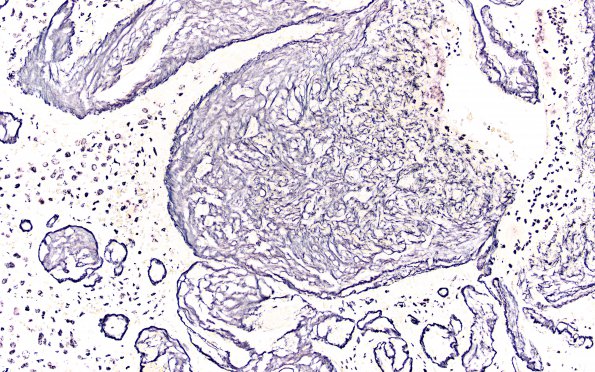

Washington University Experience | NEOPLASMS (GLIAL) | Pleomorphic Xanthoastrocytoma (PXA) | 17F PXA Anaplastic WHO III (Case 17) Retic 20X

A reticulin stain shows an increased perivascular meshwork albeit without any conspicuous increased pericellular staining in the solid areas of tumor.